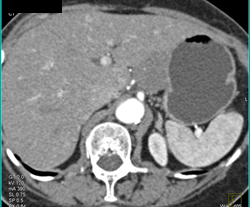

Gastric Varices in Portal Hypertension